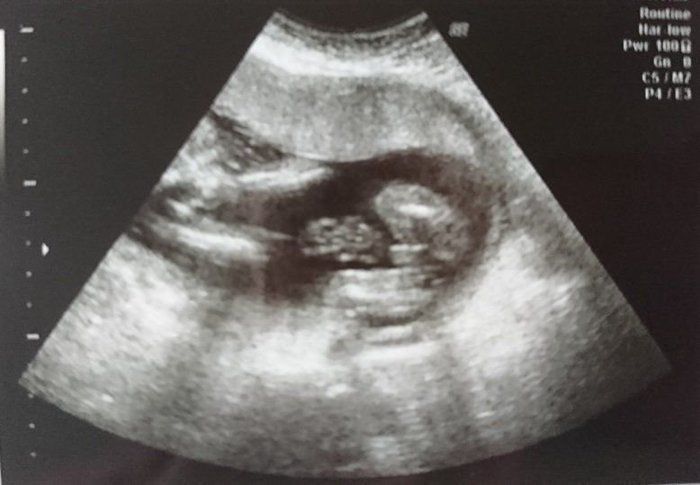

犬飼ねこさんの妊娠18週目のエコー写真

手の指がはっきりと見えます。

頭の骨がしっかりしてきました。ムンクの叫びのよう。

おしりの画像です。この日、女の子と判明。